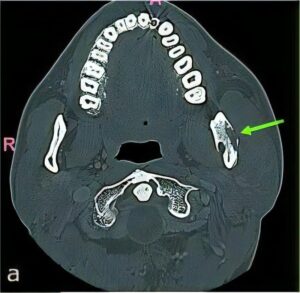

のう胞

のう胞は、何らかの理由で“水を含んだふくろ”ができてしまう病気です。特に顎骨は、のう胞ができやすいと言われています。

顎骨ののう胞では、虫歯から発生する「歯根嚢胞」が大半を占めていますが、くちびるにできる「粘液嚢胞(唾液が貯まった嚢胞)」や「含歯性嚢胞(埋伏歯にできる)」など様々な種類があります。

当科ではCT、MRI、病理組織診(良性悪性の確認検査)などの検査・診断、および治療(手術)を行っています。